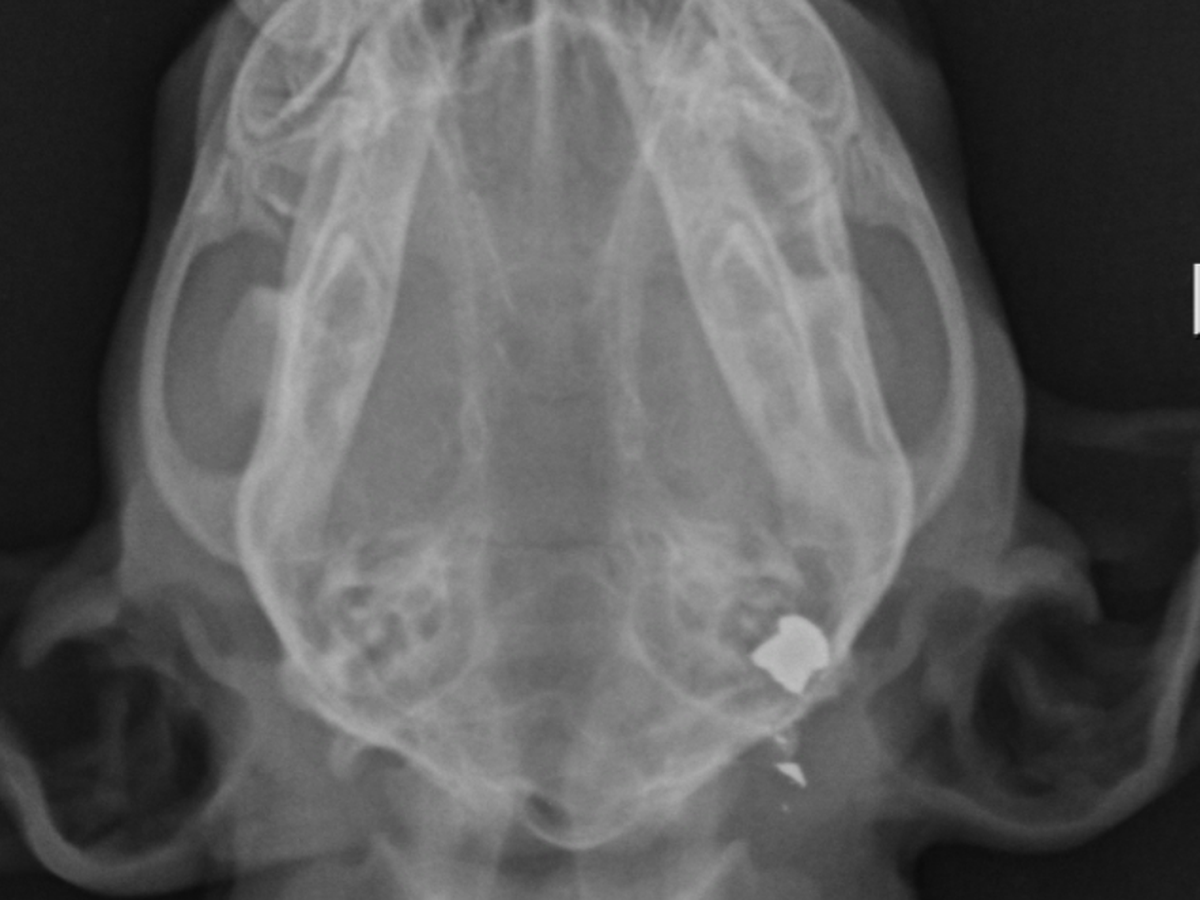

On Friday someone shot our 3 month old chihuahua puppy that we were fostering. Little Chloe was a sweet playful puppy. She had been adopted and was waiting to be taken to her forever home. Some HORRIBLE person with no heart or soul took that from her by shooting her. She was outside Friday morning in my back yard playing as normal, her and her brother crawled under the fence and went into our neighbors yard and that is where I found her. . We first thought a hawk got her but once she had x-rays done of her little body we got the horrible news that she had been shot with a pellet gun. The pellet is in the back of her little skull. We are doing everything we can. She is being monitored very closely. The medicines are expensive that she needs to avoid any brain bleeding. We are asking for your help. Medicines and vet bills are adding up. We want to do all we can to save her. If she makes it she will need to see a specialist, have a CT scan, and have surgery to remove the pellet inbedded in the back of her little head, and then her rehabilitation. We have her at a vet in Tijuana but her situation is still costly even there. Anything will help. I will post updates. We ask for all your prayers for Little Chloe.